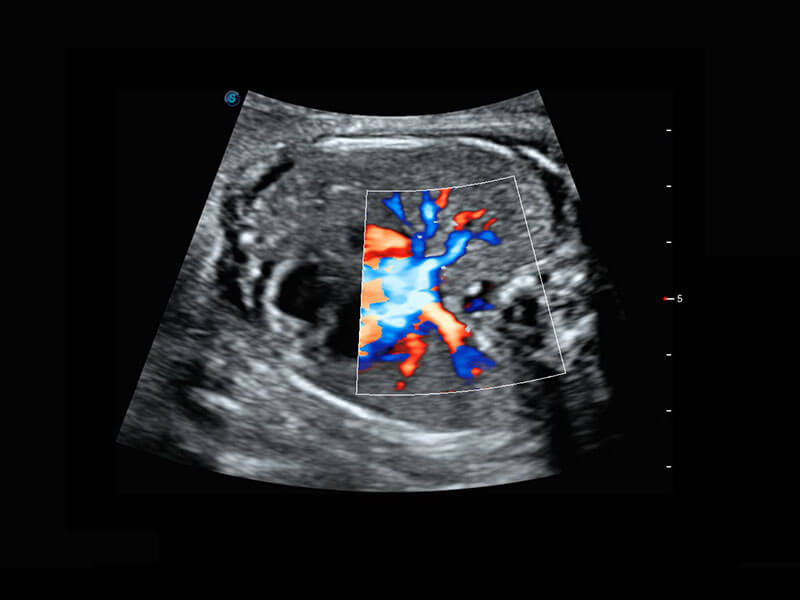

胎兒體循環(huán)